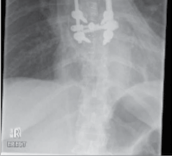

Figure 4.3 A fracture dislocation of the thoracic spine stabilised with posterior thoracic rods and screws.